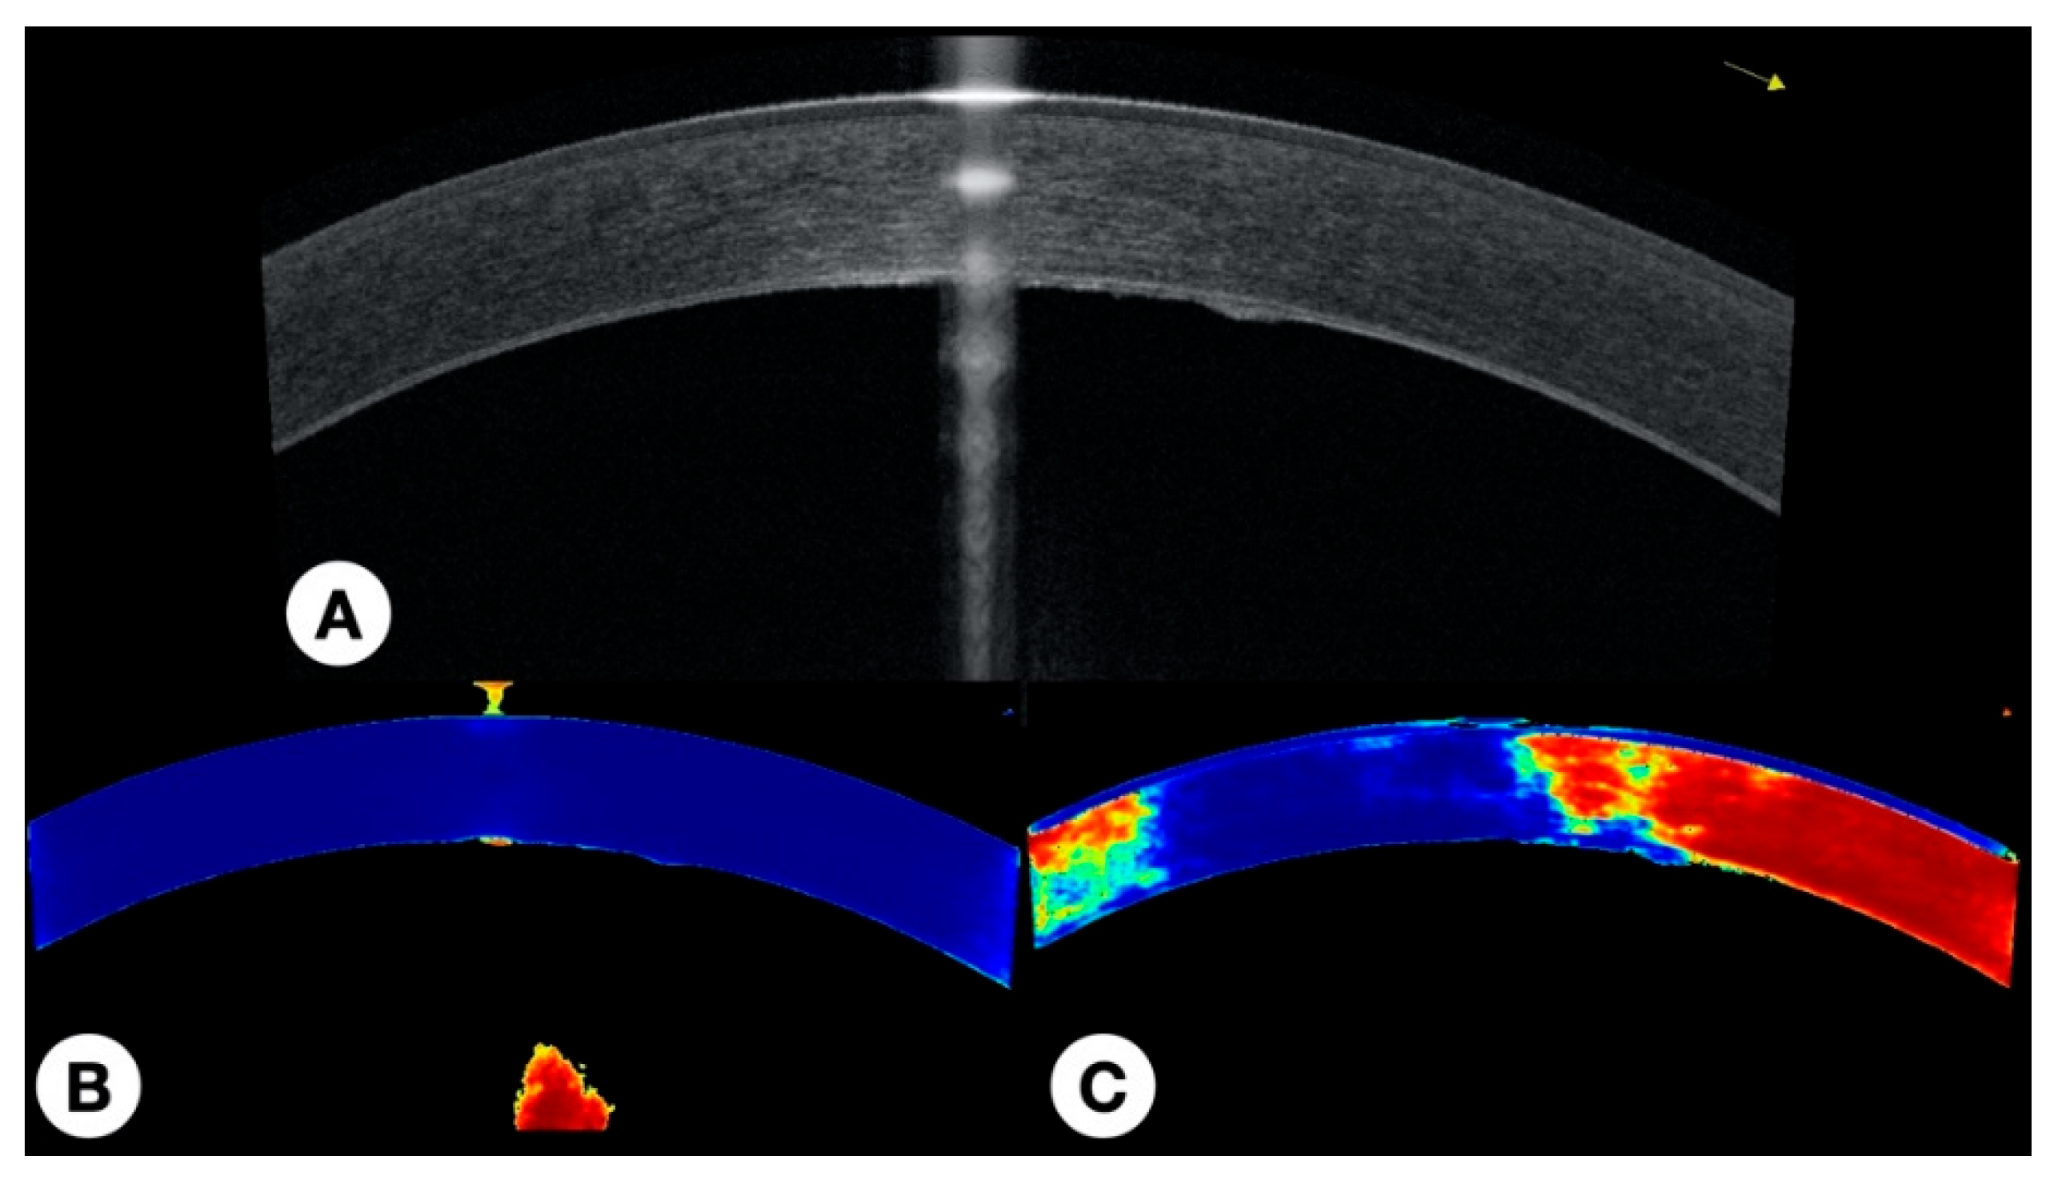

2.5.4. Visual Representation of the Results